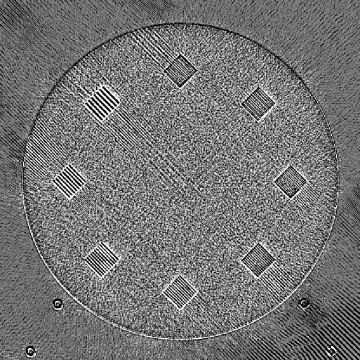

Refer to caption

(a)

(b)

Figure 9: (a) The ACR phantom module 1 with 4 different inserts for CT number fidelity testing. In addition, two ramps of wires are visible near the phantom center. The image display window center is 150 HU and window width is 700 HU. (b) The phantom module 3 with a uniform water-equivalent radiodensity of 0 HU. The display window center is 0 HU and window width is 400 HU.

To evaluate image quality, we first tested the performance of JENG on a standard CT phantom, CT ACR 464 phantom 35. Then we tested JENG on 5 clinical thoracic datasets and 3 abdominal datasets. The ACR 464 phantom contains four modules in total, with each module 40 mm in depth and 200 mm in diameter. The first module has 4 different inserts to test CT number fidelity. In addition, the module contains a series of wires for cross-plane resolution evaluation, shown as white horizontal bars near the center in Fig. 9(a), and are visible in 0.5 mm z-axis increments. The second module tests low contrast resolution, but is not used in this paper. The third module, shown in Fig. 9(b), is a uniform cylinder of water-equivalent material of 0 Hounsfield units (HU), and we used this module to quantitatively measure image noise profile and in-plane resolution. The fourth module consists of resolution bars of various spatial frequencies for analysis on high contrast resolution. To scan the phantom, the scanner setup used dual sources with 2 focal spots at each source. In addition, the projections were acquired using the same protocol for clinical thoracic scans with 100 KV, a nominal tube current of 718 mA and a high helical pitch of 2.8. For all experiments, we compared JENG against the state-of-the-art Siemens ADMIRE, reconstructed with a BL-64 soft tissue sharp kernel, and we define ADMIRE as the clinical standard hybrid IR method for the rest of the paper.